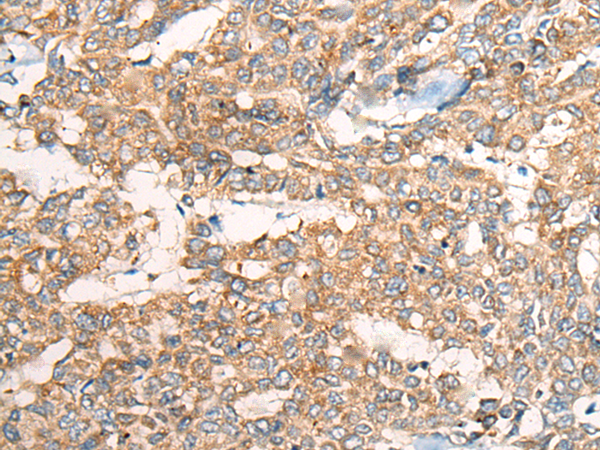

分类: 科研抗体货号: P12854别名: JEDI; MEGF12应用: IHC反应种属: Human, Mouse